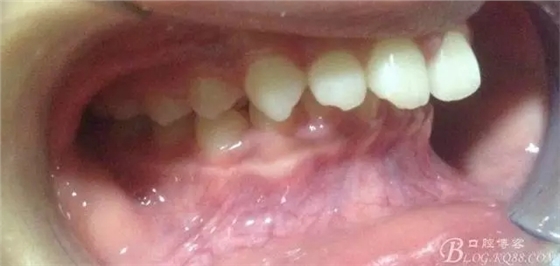

術前側貌,下合后縮還算明顯,正面照有點看不出的樣子!